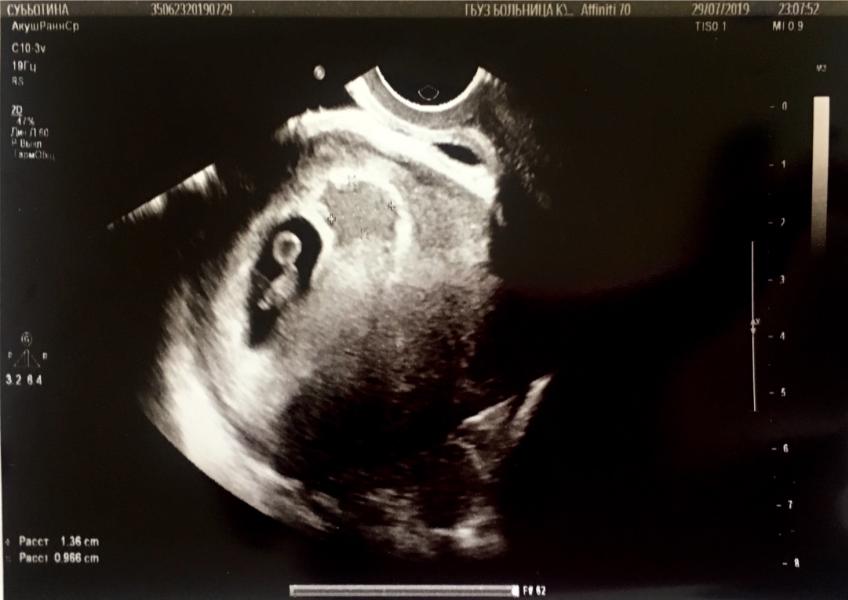

Ну вот и пришёл долгожданный день ))) сделали узи - ходили с мужем )))

Имеется 1 живой плод, и гематома которая уже как бы рассасывается , вроде ничего страшного , но назначили «или /или» Дюфастон или Утрожестан 200.

Срок совпадает с менструальным сроком , сегодня ровно 7 недель по срокам и размерам .